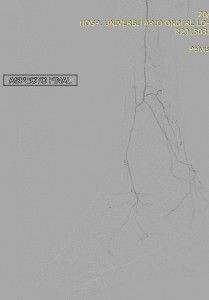

Nesta última imagem, observa-se o fluxo pela Fibular opacificando parcialmente o Arco Plantar via ramos tarsais. Note-se que o extenso grau da doença aterosclerótica obstrutiva ainda impede a opacificação das artérias do ante-pé. Apesar destes achado angiográficos a paciente referiu significativo alívio da sintomatologia dolorosa.